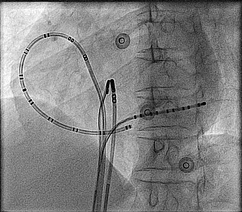

Catheters

afl_catheters.jpg